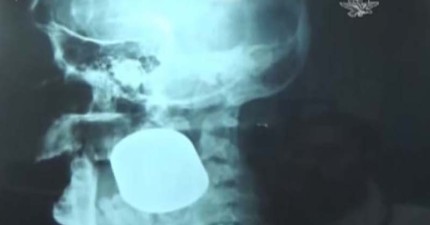

墨西哥這位女攤販經歷了一場意外,結果卡在臉上的東西連醫院都不知道是什麼…?

February 28, 2015

世界